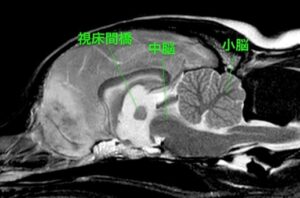

MRI検査では左の前頭部に巨大な腫瘤が認められた。腫瘤は近くの髄膜と連続しているように見えることから髄膜腫が最も疑われた。